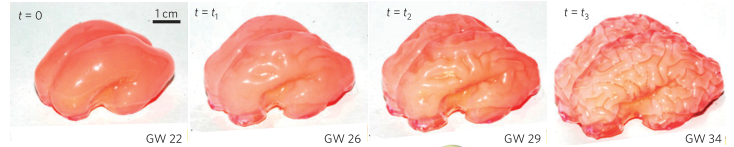

Cerebral folding

Tensional and compressive forces result in cerebral folding.

Note:

- Tensegrity, tensional forces of long cellular processes (axon bundles), Felleman and Van Essen 1991 monkey neocortical/visual wiring map 2

Takes between 22 – 26 weeks of gestation (154 – 182d. or 5.1 – 6 mo.) before fissures and gyri start forming in the human brain (Tallinen Nature Physicis 2016). Between 33–37 weeks the convolutions take on the complexity seen in the newborn human brain (7.7–8.6 mo.).

Defects in cortical development

- lissencephaly: smooth brain

- do not have characteristic gyri patterns

- leads to death, severe epilepsies and mental retardation

- cause is defects in neural migration during development

Note:

Gyrification from constrained cortical expansion

[^Tallinen:2014] http://dx.doi.org/10.1038/nphys3632